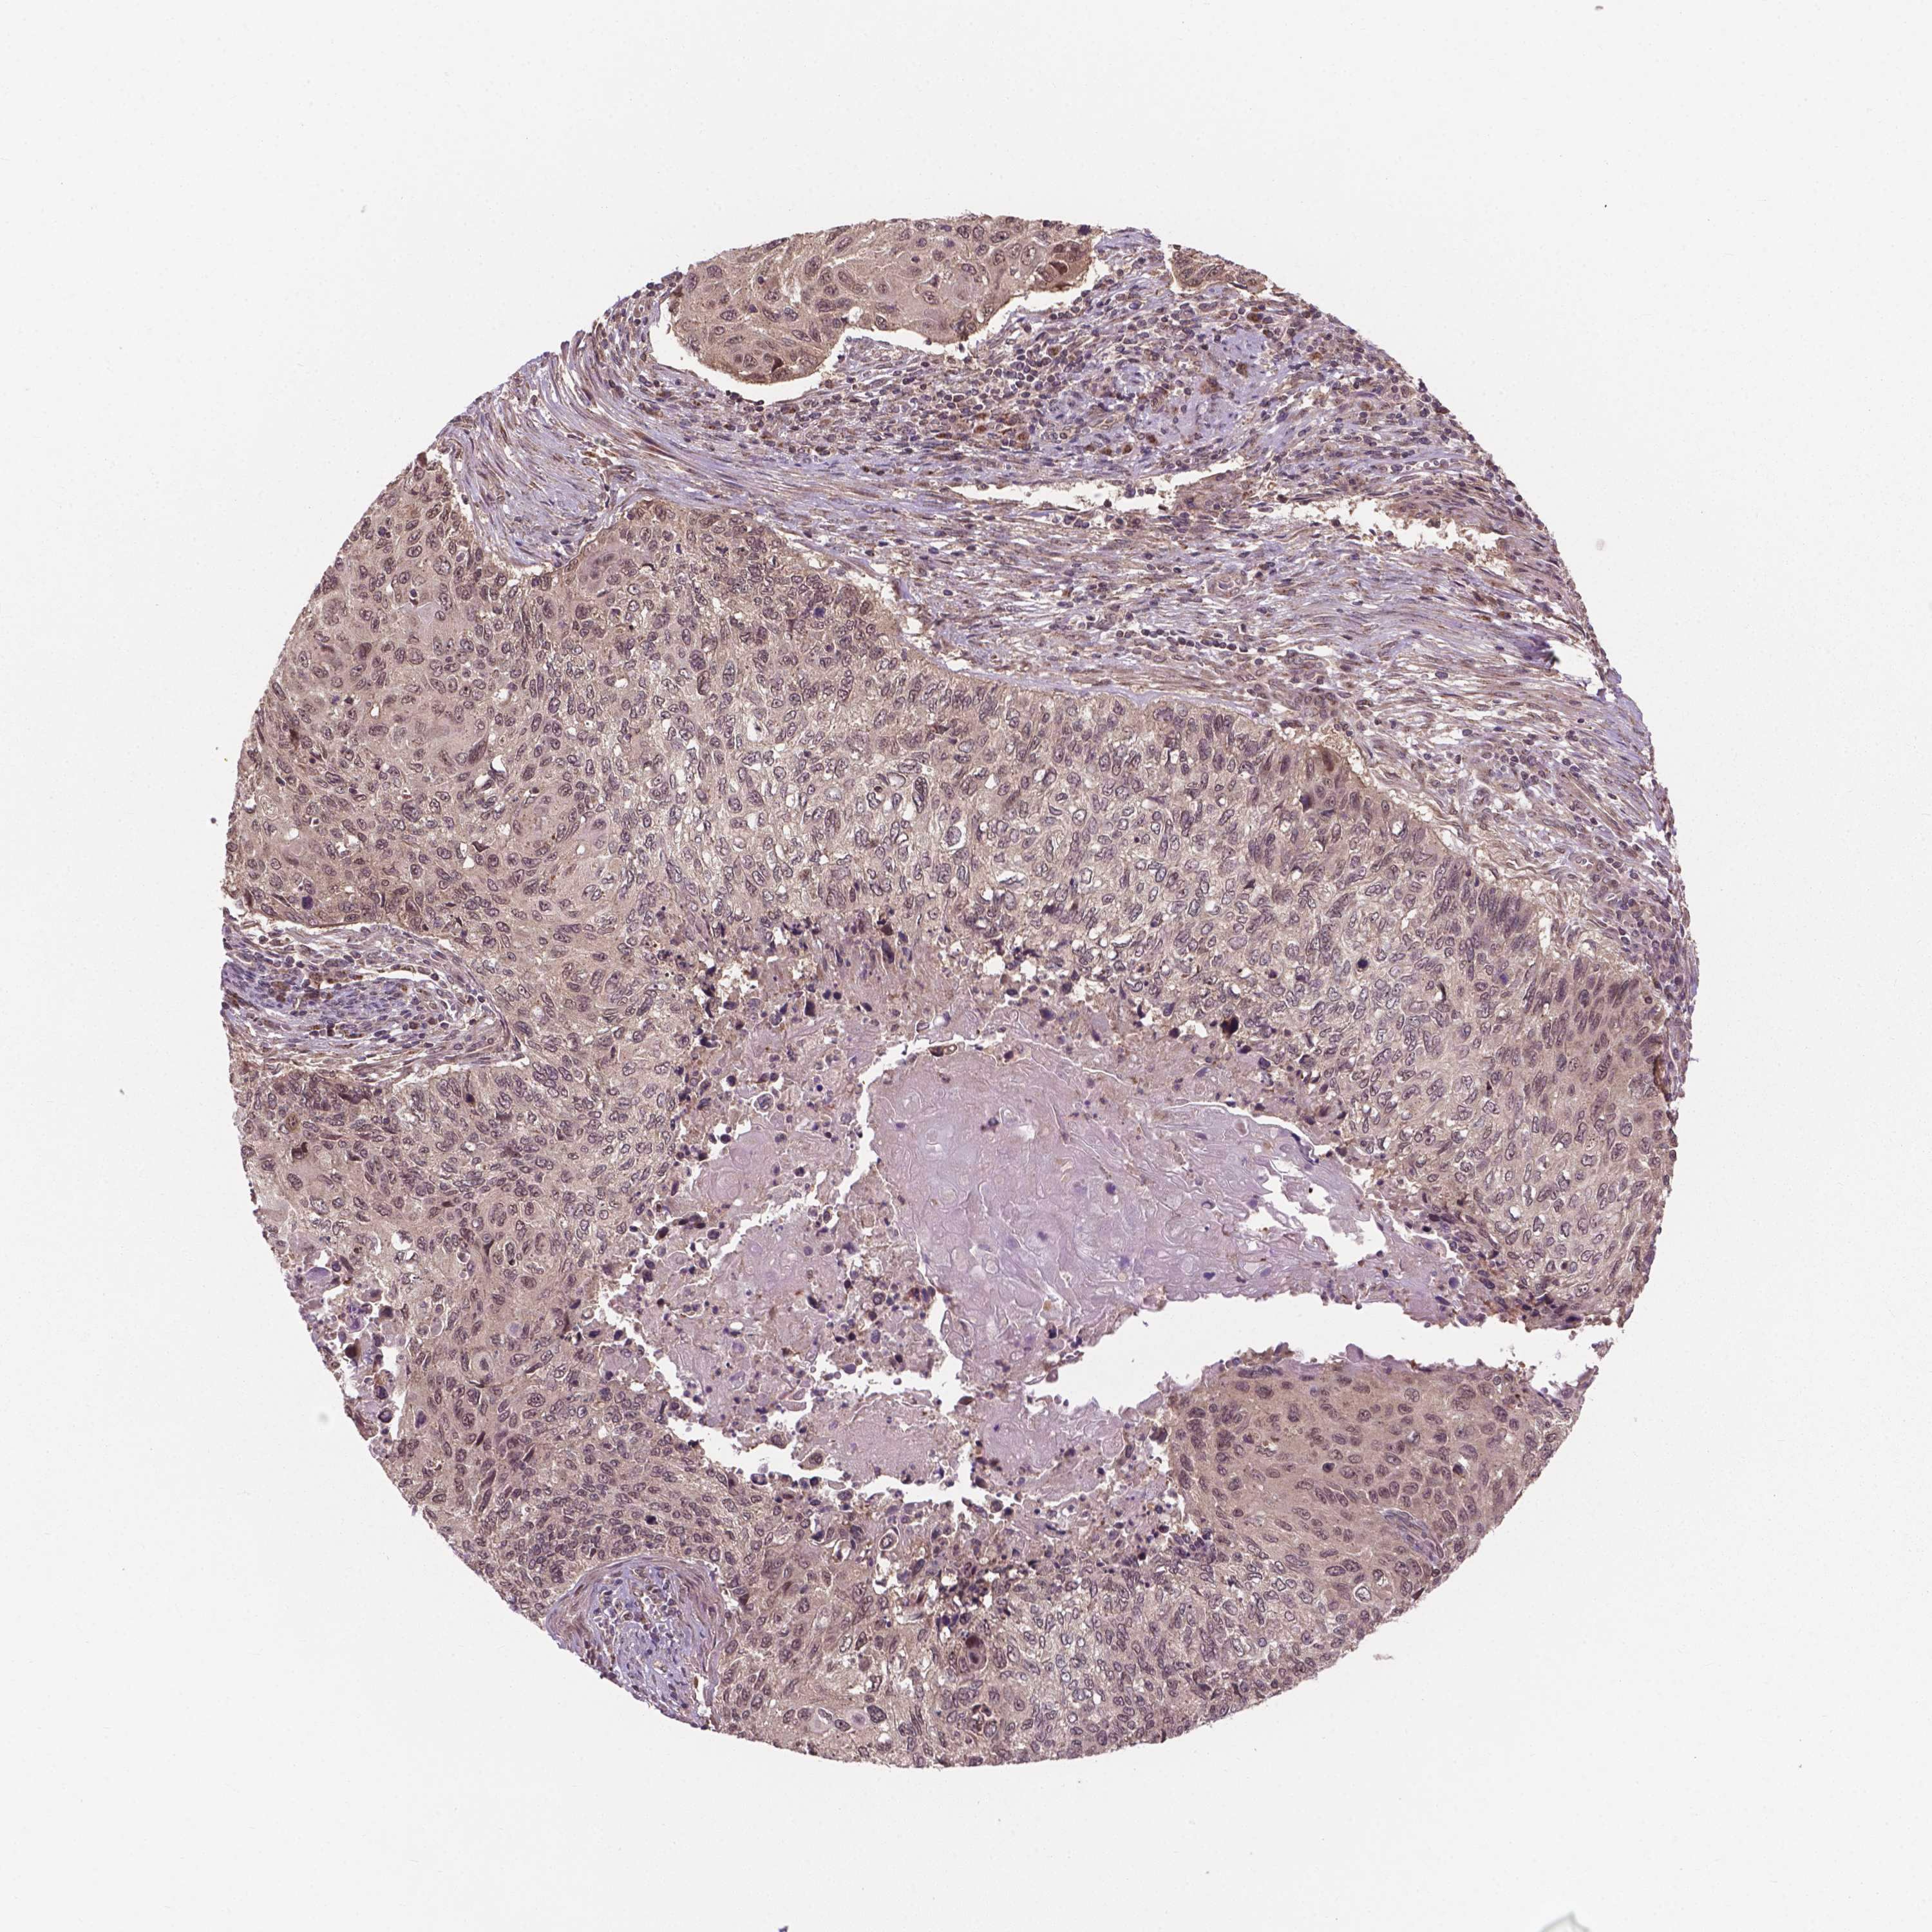

CERVICAL CANCER - Protein expressioni

A mouse-over function shows sample information and annotation data. Click on an image to view it in a full screen mode. Samples can be filtered based on level of antibody staining by selecting one or several of the following categories: high, medium, low and not detected. The assay and annotation is described here.

Note that samples used for immunohistochemistry by the Human Protein Atlas do not correspond to samples in the TCGA dataset.

Antibody stainingi

Antibody staining in the annotated cell types in the current human tissue is reported as not detected, low, medium, or high, based on conventional immunohistochemistry profiling in selected tissues. This score is based on the combination of the staining intensity and fraction of stained cells.

Each image is clickable and will lead to virtual microscopy that enables deeper exploration of all samples and also displays staining intensity scores, fraction scores and subcellular localization as well as patient and tissue information for each sample.

Antibody HPA065425

Antibody CAB069426

Squamous cell carcinoma, NOS

Adenocarcinoma, NOS